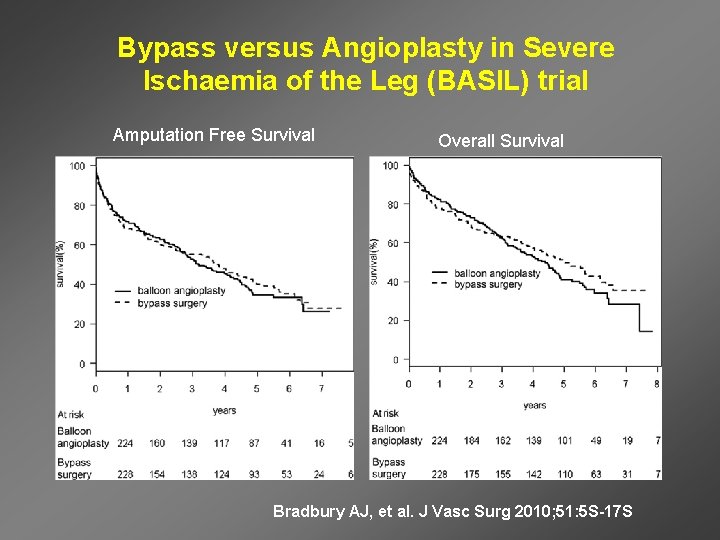

Bypass versus Angioplasty in Severe Ischaemia of the Leg (BASIL) trial Amputation Free Survival Overall Survival Bradbury AJ, et al. J Vasc Surg 2010; 51: 5 S-17 S